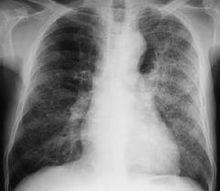

乾酪性肺炎(cascouspneumonia)為小兒原發性肺結核中最嚴重的病型之一。在小兒抵抗力非常低下,對結核菌的過敏反應十分增強的情況下,帶有大量結核菌的乾酪樣物質進入肺組織即可造成乾酪性肺炎。最多見為支氣管淋巴結乾酪樣物質破潰入支氣管引起;有時可能為原發灶液化崩潰進一步擴散而成;肺內新鮮的血行播散性結核病變可迅速融合溶解變成小葉性乾酪性肺炎;此外在續發性肺結核浸潤性病變可呈現大量乾酪樣壞死變成乾酪性肺炎,但較少見。大葉性乾酪性肺炎多見於嬰幼兒,小葉性者則多見於較大兒童。前者起病多較急,有高熱和嚴重中毒症狀,後者可較緩,有長期低熱和慢性中毒症狀。多有咳嗽、吐痰甚至咯血。肺部可聽到支氣管呼吸音或管狀呼吸音,及大量響亮中、小水泡音。X線攝片在大葉性乾酪性肺炎可見大片濃密陰影,內有透亮區;在小葉性乾酪性肺炎可見兩肺散在密度不均之團塊狀陰影,內有蜂窩狀透亮區或大小不等之無壁空洞血象可見:中性多形核粒細胞高度增多及核左移現象,血沉加速,痰及胃液中可找到大量結核桿菌。

乾酪樣肺炎X線表現:一個肺段或肺葉實變,密度不均勻,輪廓與大葉性肺炎相似,但密度較大葉性肺炎為高。多發生於右肺上葉,用高電壓攝片或斷層攝影時,其中有多處不規則的蟲蝕樣空洞影。該肺葉往往因有纖維化而部分萎陷。其餘肺野可伴有支氣管播散,而形成多數散在的小葉性乾酪性肺炎